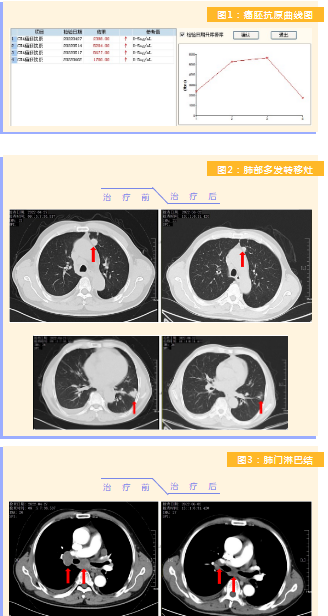

患者完成1周期治療后,上腹部疼痛癥狀基本消失,梗阻性黃疸癥狀緩解,腫瘤指標(biāo)下降(圖1),肺部多發(fā)轉(zhuǎn)移灶消失和縮小(圖2),雙肺門淋巴結(jié)縮小(圖3),肝臟多發(fā)轉(zhuǎn)移灶縮?。▓D4)。